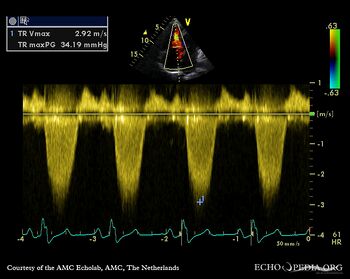

Ebstein anomaly and non-compaction cardiomyopathy

Continuous-wave Doppler signal of tricuspid regurgitation, pulmonary hypertension A2CH: non-compaction of left ventricle